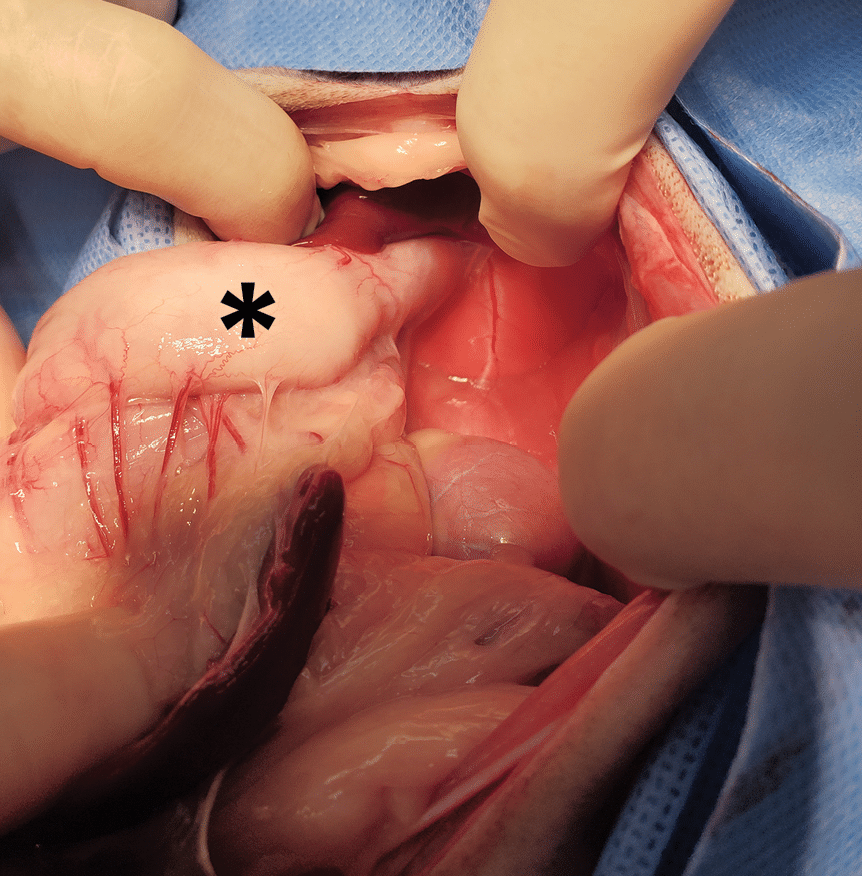

The cat was taken to surgery for abdominal exploratory and right nasal reconstruction. The cat was first positioned in dorsal recumbency, and a midline celiotomy was performed. The entire stomach was located in the abdominal cavity, but the distal esophagus, fundus, and proximal portion of the gastric greater curvature were thickened and white, with a finely cobblestoned surface (FIGURE 4). To treat the sliding hiatal hernia, the esophageal hiatus was narrowed with interrupted 3-0 polydioxanone sutures placed in the dorsomedial margins of the right and left pars lumbalis, and an esophagopexy was performed along the ventral and lateral borders of the phrenicoesophageal junction. An ovariohysterectomy was also performed before routine abdominal closure.

Figure 4. Thickening and scarring of the proximal gastric greater curvature (asterisk) from sliding hiatal herniation.